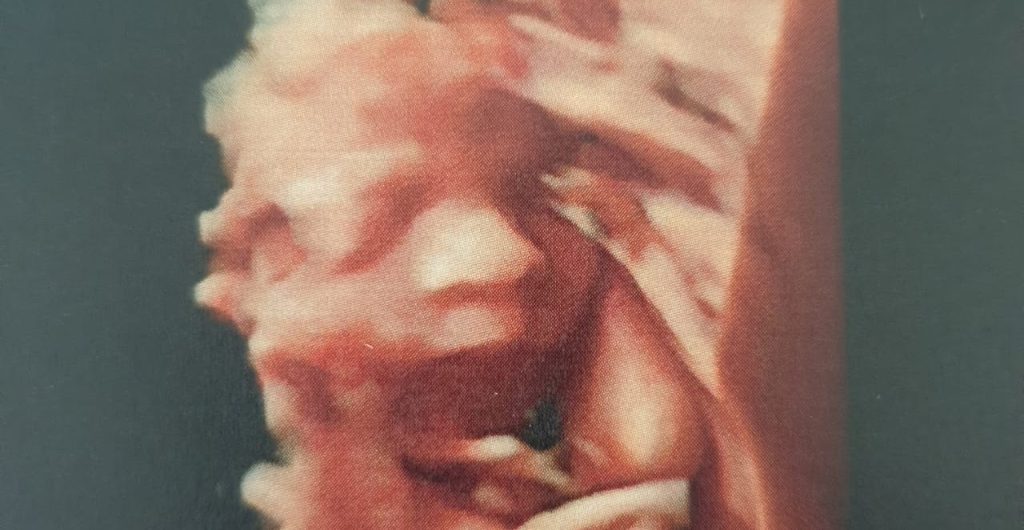

¡Bendita tecnología! Les presentamos al pequeño Lucas Simón, que con 6 meses de gestación es el primer hijo de Sofía (Investigación UC).

Sofi nos comentó que su embarazo ha sido muy tranquilo y que está muy contenta en la espera de su guaguita. ¡Felicitaciones por tan linda noticia!